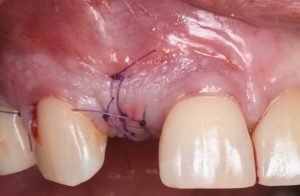

The procedure is presented step by step, including flap design and management, defect assessment, membrane selection and stabilization, flap advancement, and suturing techniques. Emphasis is placed on achieving tension-free closure and maintaining hard and soft tissue contours critical for esthetic success.

- Suturing techniques to protect the regenerative site